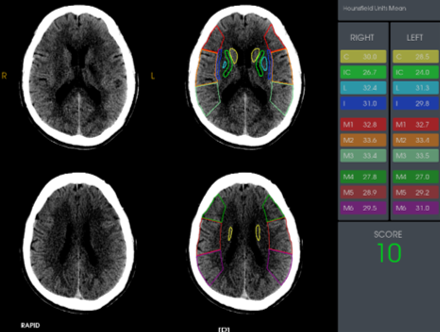

近期,我院高级卒中中心引进了脑卒中头颅“一站式”ct检查又称多模式头颅ct成像,包括ct平扫(ncct),ct血管成像(cta)和ct灌注成像(ctp)。目前省内仅有我院及中南大学湘雅医院、湘潭市中心医院三家医院应用了该项技术。该项技术的目的是扩大取栓治疗时间窗,使更多的患者从取栓治疗中获益。通俗的说,“时间就是大脑”的抢救理念倡导的是,一旦发生卒中征兆,立即送至有静脉溶栓、机械取栓资质的医院救治。对于明确发病4.5h以内的急性缺血性脑卒中患者,来了医院之后先做一个ct平扫检查,排除脑出血的情况,在无禁忌症的前提下,建议实施静脉溶栓治疗,早发现早治疗早获益。但是对于发病6-24h的患者或发病时间不明确的患者,ct平扫上是很难看到梗死表现,梗死的表现一般到24小时之后才会出现。那怎么来显示这部分组织?那就是进行“ct灌注成像”,可以看到具体的梗死区域、可挽救的缺血半暗带、同时利用ctp数据进行头部cta重建和侧枝循环评估,为下一步的治疗方案提供量化标准。但是做ct、cta再做ctp无疑时间线就拉长了,与“时间就是大脑”的理念相违背。那有没有一项技术将这三项检查紧密联系起来,有效缩短检查时间?这便是头颅“一站式”ct检查,既为脑卒中患者的救治赢得了宝贵的时间,又如同徕卡相机一样精准、高清的成像,帮助医生快速拟定治疗方案。

多模式头颅ct成像和侧枝循环评估